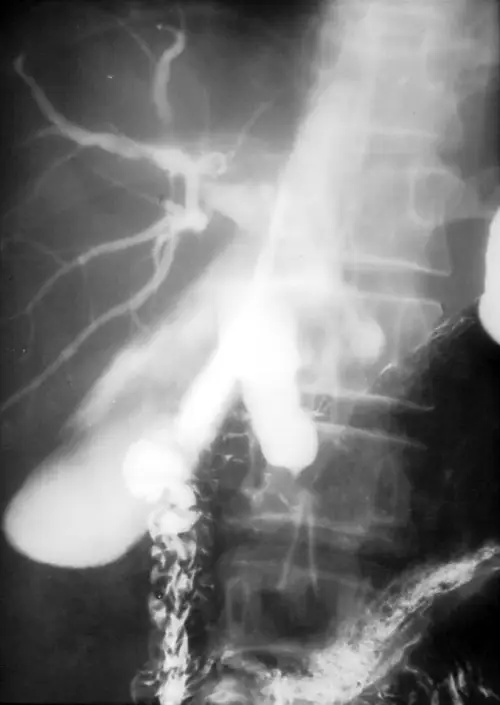

本題考核胰臟頭癌(pancreatic head cancer)的典型臨床表現與影像診斷。老年男性出現疲倦、食慾減退、皮膚黃疸(obstructive jaundice),合併 CA 19-9 升高,搭配 CT 及膽道攝影影像,是胰臟頭癌的典型呈現。

影像一(膽道攝影 / ERCP cholangiogram): 可見肝內膽管明顯擴張,樹枝狀膽道系統顯影清晰,下方膽管出現截斷(abrupt cutoff),符合膽管遠端受壓阻塞的表現。同時可見胰管與總膽管同時擴張的「雙管徵(double duct sign)」,此為胰臟頭部或壺腹周圍腫瘤的高度特徵性影像表現。